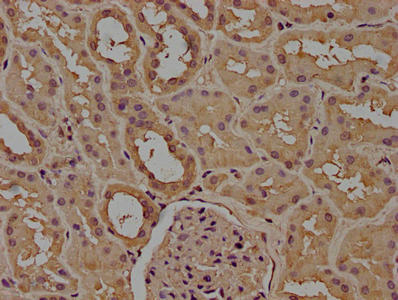

10 μg, 100 μg - Cubilin antibody [orb4997]Featured

ICC, IF, IHC-P, WB

Human, Mouse, Porcine, Rat

Rabbit

Polyclonal

Unconjugated